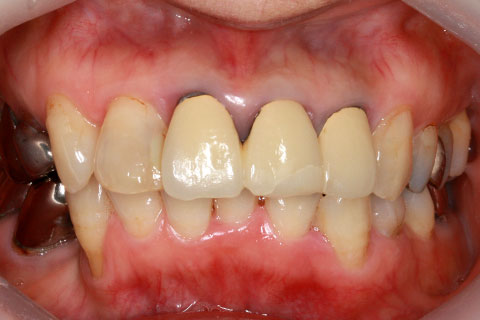

オールセラミックの症例2

- 年齢・性別

- 45歳男性

- 治療期間

- 2ヶ月

- 抜歯

- なし

- 治療費

- 70.4万円

- 備考

- 前歯8本の歯列不正によるセラミック治療

- 治療内容

- 歯質を削除し、セラミック冠をセメント合着

- 施術の副作用(リスク)

- 知覚過敏、歯髄炎、荷重負担